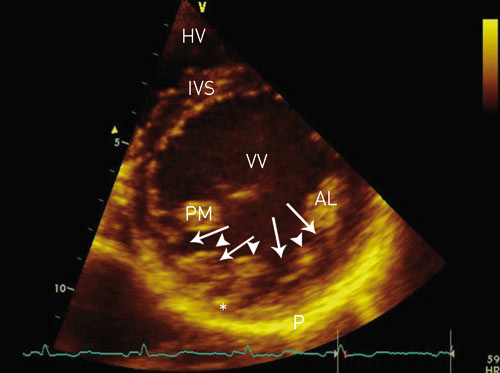

Manglende modning av venstre ventrikkel er rapportert å forekomme hos mindre enn 1 % av pasientene i forskjellige ekkokardiografiske materialer og kan foreligge som familiær disposisjon. Tilstanden er ganske nylig beskrevet som en årsak til dysfunksjon av venstre ventrikkel (1) – (6) og skyldes feil i den endomyokardiale embryogenesen (1). Den kan både hos barn og voksne medføre hjertesvikt, systemiske embolier og/eller ventrikulære arytmier (1, 2, 7) – (9). Diagnosen stilles ved todimensjonal ekkokardiografi eller MR av hjertet (5, 7, 9) – (12). Typisk påvises venstre ventrikkels myokard med et tynnere og normalt utviklet ytre lag, mens det indre laget mot endokard er trabekulært fortykket, med dype intertrabekulære recesser (fig 1).

Under embryogenesen består hjertet av et nettverk av muskelfibre som normalt fortettes, og de intertrabekulære sinusoidene degenerer. Denne myokardmodningen (compaction) foregår i 5. – 8. svangerskapsuke og medfører at de intertrabekulære sinusoidene omdannes til kapillærer. Prosessen starter fra epikard og fortsetter innover til endokard, fra basis av hjertet til apex, og er mer fullkommen i venstre ventrikkel enn i høyre. Samtidig utvikles den koronare sirkulasjonen (1, 13). Ved manglende modning går denne prosessen i stå. Dette resulterer i multiple persisterende og tydelige ventrikulære trabekler og dype intertrabekulære recesser som kommuniserer med ventrikkelkaviteten og ikke med koronarsirkulasjonen (fig 1, fig 2). De intertrabekulære recessene og ventrikkelkaviteten er kledd med sammenhengende endotel (1, 2, 5). Predileksjonssteder for denne manglende modningen, som man ellers finner normalt hos fisker, amfibier og krypdyr (4), er venstre ventrikkels midtre og distale segmenter av laterale og nedre vegg samt apexavsnittet (5, 9, 13). Graden av endringer varierer fra pasient til pasient (1, 4).

Etter hvert har man fått økt kunnskap om patogenese, diagnostikk og prognose, og tilstanden er nylig blitt klassifisert som en primær kardiomyopati (17). Ekkokardiografi eller MR-undersøkelse (12) av hjertet angis som gullstandard for diagnostikk. Flere ekkokardiografiske funn angis som typiske (2, 5, 7, 9) – (11):

fravær av andre hjertemisdannelser (per definisjon).

affeksjon av apex og/eller apikale og/eller midtventrikulære segmenter av nedre og/eller laterale vegg. Mer enn 80 % av pasienter med denne tilstanden har manglende modning på ett eller flere av disse predileksjonsstedene.

tre eller flere uttalte myokardtrabekler vurdert i samme bildeplan.

dype intertrabekulære recesser som kommuniserer med ventrikkelkaviteten.

de affiserte myokardavsnittene er tolaget, bestående av et tynt ytre epikardialt lag og et fortykket trabekulært indre endokardialt lag.

det ytre myokardlaget er fortettet på normal måte, mens det indre laget ikke er fortettet. Ved måling av tykkelsen av veggsegmentene i endesystolen, vil forholdet mellom det ikke-fortettede og det fortettede laget typisk være > 2,0.